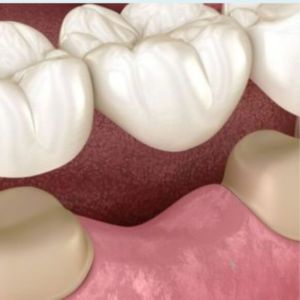

CROWNS AND BRIDGES

CROWNS AND BRIDGES

CROWNS AND BRIDGES

CROWNS AND BRIDGES